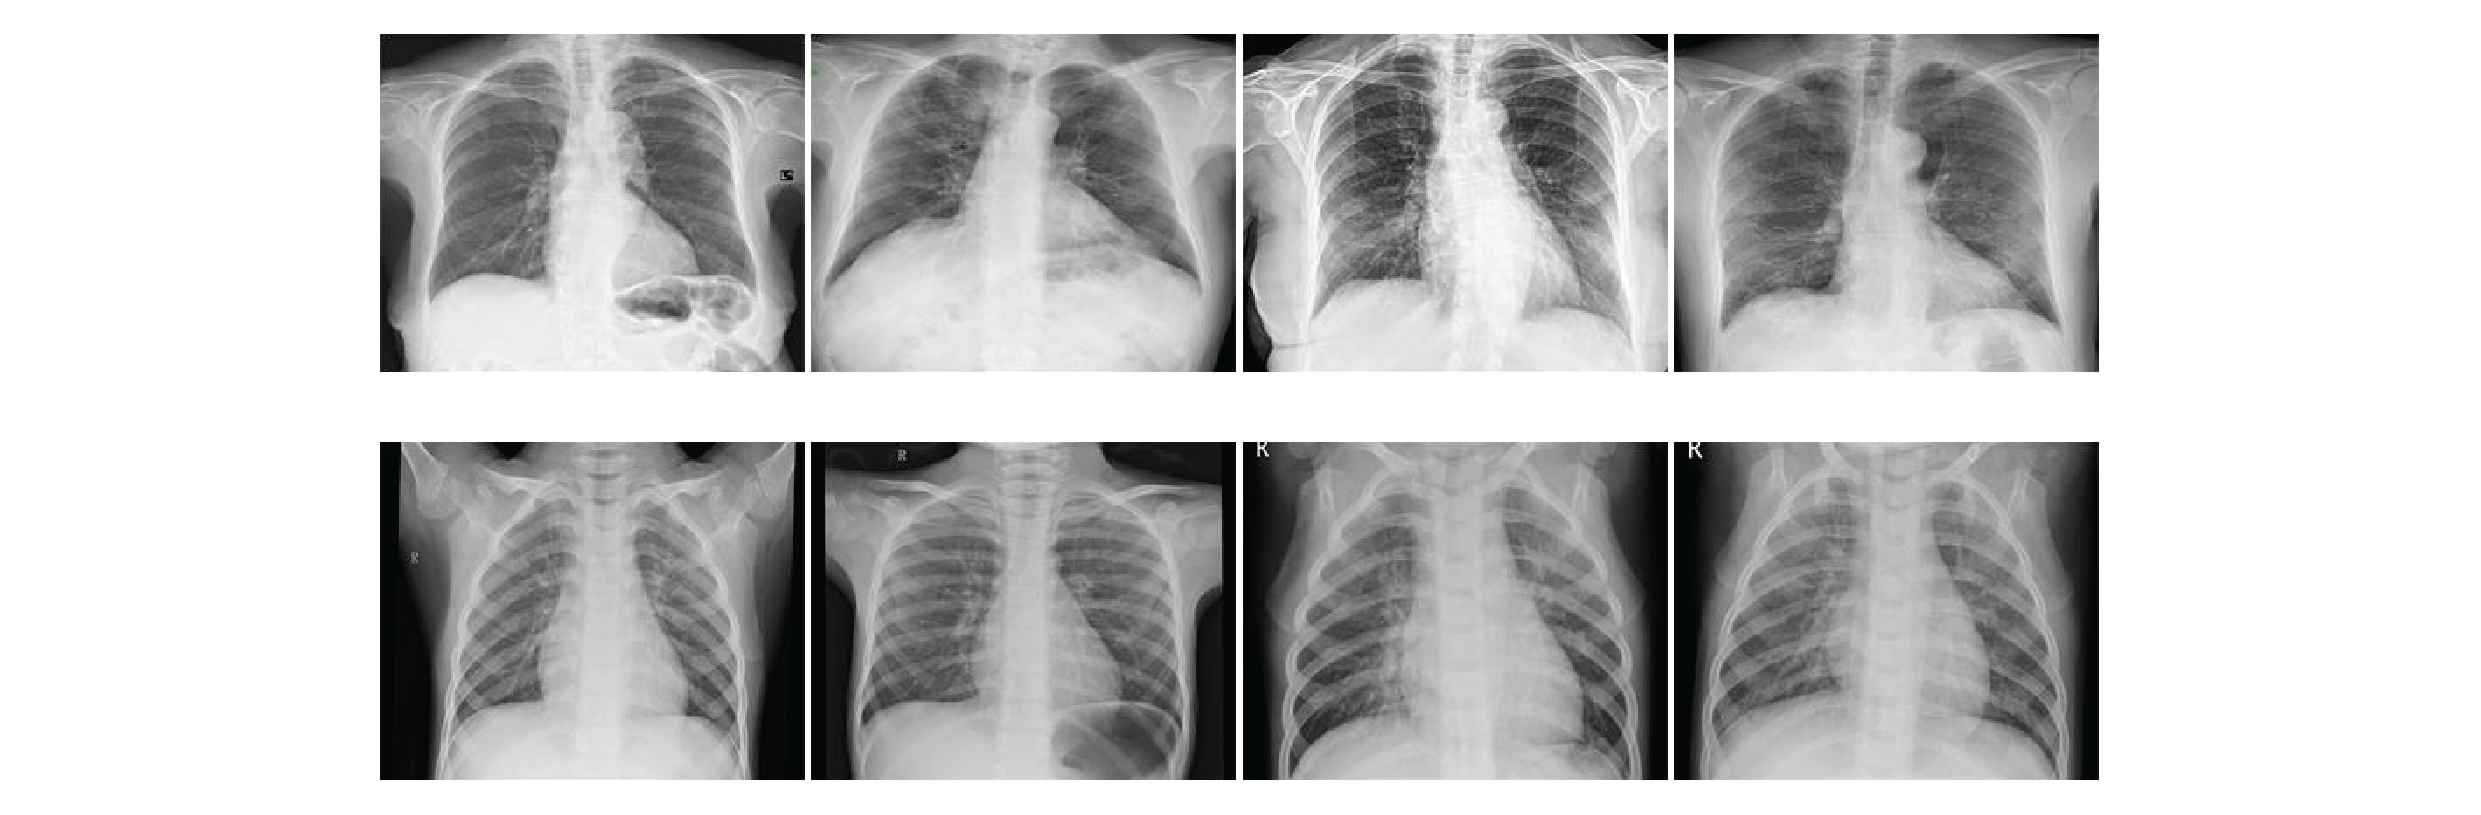

In our work we have used two open-source datasets. The COVID-19 chest X-ray image datasets is from GitHub (https://github.com/ieee8023/covid-chestxray-dataset), which was prepared by Ref. [31]. This datasets consists of X-ray and CT scan images of different patients infected with COVID-19 and other pneumonia. It has a total of 760 images. We selected 412 X-ray images of COVID-19 positive patients. The second datasets comes from Kaggle's chest X-ray images (pneumonia) (https://www.kaggle.com/paultimothymooney/chest-xray-pneumonia), this datasets consists of chest X-ray images of normal and common pneumonia patients, which contains 5863 chest X-ray images. We selected 4265 X-ray images of pneumonia and 1575 normal X-ray images from this datasets. Our training set contains 5526 X-ray images, including 310 COVID-19 patient images, 1341 normal images and 3875 pneumonia. The test set contains 726 X-ray images, including 102 COVID-19 patient chest X-ray images, 234 normal chest X-ray images and 390 chest X-ray images of common pneumonia. The chest X-ray images of various patients in our datasets are shown in Figure 7.

Chest X-ray images.

From the above figures, it can be seen that the chest X-ray images have high inter-class similarity and low intra-class variance, which increases the difficulty of the network to classify chest X-ray images.